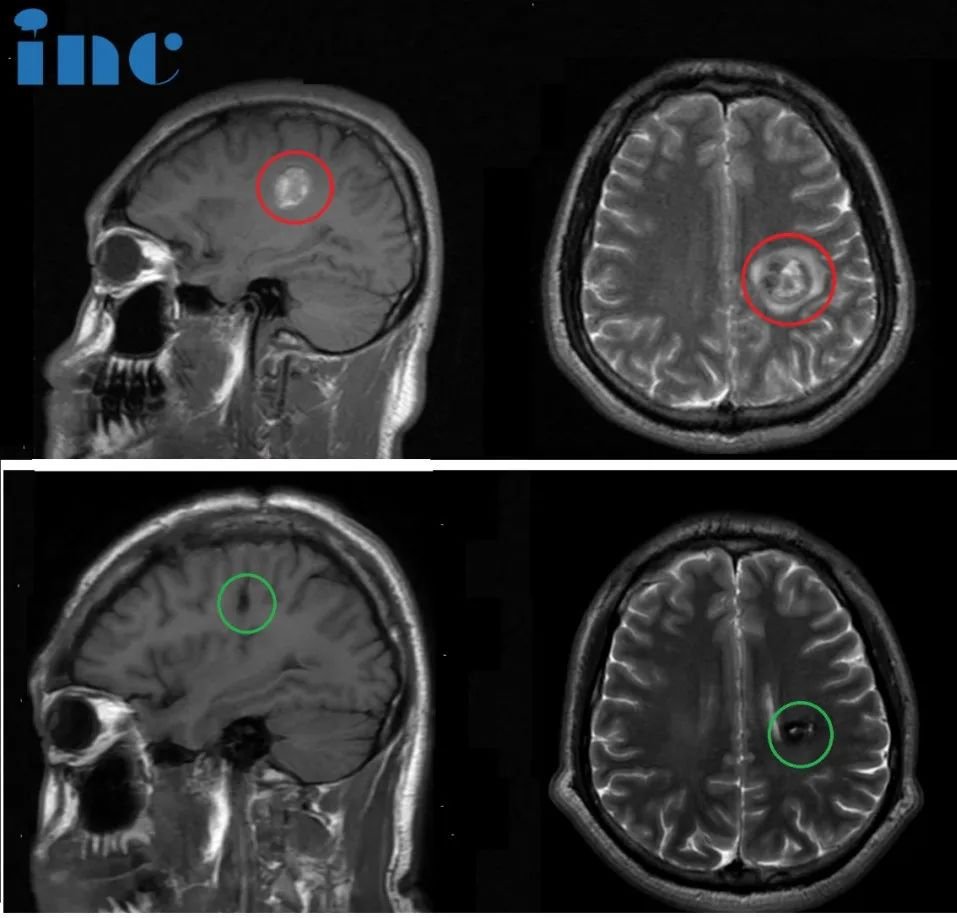

简要病史:47岁的邓女士事业如日中天,对于工作,有着较强的责任心及较高的自我要求。一次定期体检却发现右脑额叶深部占位,大小约8mm,医生判断是海绵状血管瘤。咨询了上海的专家,但是医生的解释让他害怕,不建议手术,因为病灶部位太深,靠近功能区,手术风险大。而且目前病灶体积小,建议每年复查随访。查出海绵状血管瘤之后,邓女士发现有时工作太累了会头疼,近期还出现 6~7次无预兆性突然出现眼前漂浮物的现象,很快自行缓解。

治疗过程:2024年3月28日,巴教授中国行期间,一场疑难功能区海绵状血管瘤示范手术,成功拯救了47岁的邓女士于病魔的阴影之中。“I believe you, it’s a very (我很信任您,这是一个)就是正确的选择。”术后2小时,麻醉刚清醒,47岁的邓女士激动地用英语说出自己的术后感受,重新露出了大大的笑脸。

术后情况:手术1天,顺利出ICU,转入普通病房,交流顺畅、肢体活动正常,恢复良好。“我的手有力量,Thank you very much!”此时的邓女士回归了往日的健谈、声音洪亮、神采奕奕。术后2天,邓女士表示已经可以自主下床活动,“已经可以走来走去”,巴教授查房用中文为邓女士点赞。